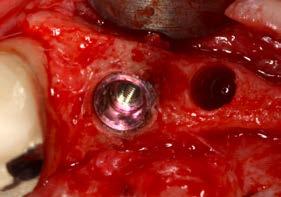

Issuu converts static files into: digital portfolios, online yearbooks, online catalogs, digital photo albums and more. Sign up and create your flipbook.